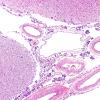

PERIPHERAL NEUROPATHY

15 NEUROPATHY ASSOCIATED WITH NEOPLASIA

1 Neoplastic Infiltration (7)